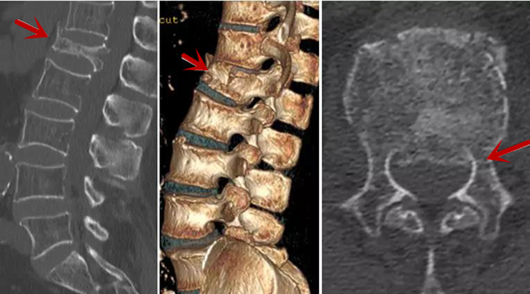

利器二:CT

CT利用X射線對(duì)人體檢查部位通過(guò)電腦切成若干層掃描,然后把每層的圖像都能顯示出來(lái)。CT相對(duì)于X光片具有更高的密度分辨力,可直接顯示X線片無(wú)法顯示的病變,觀察腰椎有無(wú)微小的骨折、骨質(zhì)有無(wú)破壞等骨質(zhì)情況、以及腰椎間盤(pán)突出、腰椎神經(jīng)根、椎管、椎間小關(guān)節(jié)的情況等。同時(shí)還可以通過(guò)后處理,重建腰椎矢狀位或冠狀位圖像,形成腰椎的3D圖像,更直觀地觀察病變部位,對(duì)腰椎手術(shù)風(fēng)險(xiǎn)具有提示作用,對(duì)手術(shù)方式的選擇具有指導(dǎo)意義,但是對(duì)神經(jīng)、脊髓損傷程度的顯示不如MRI,軟組織的分辨率仍有一定限制,對(duì)椎管內(nèi)病變顯示欠佳,且有一定的輻射。

箭頭提示椎間盤(pán)突出

從左向右依次為CT矢狀位重建圖像、三維重建圖像、軸位掃描圖像,箭頭提示腰1椎體爆裂性骨折